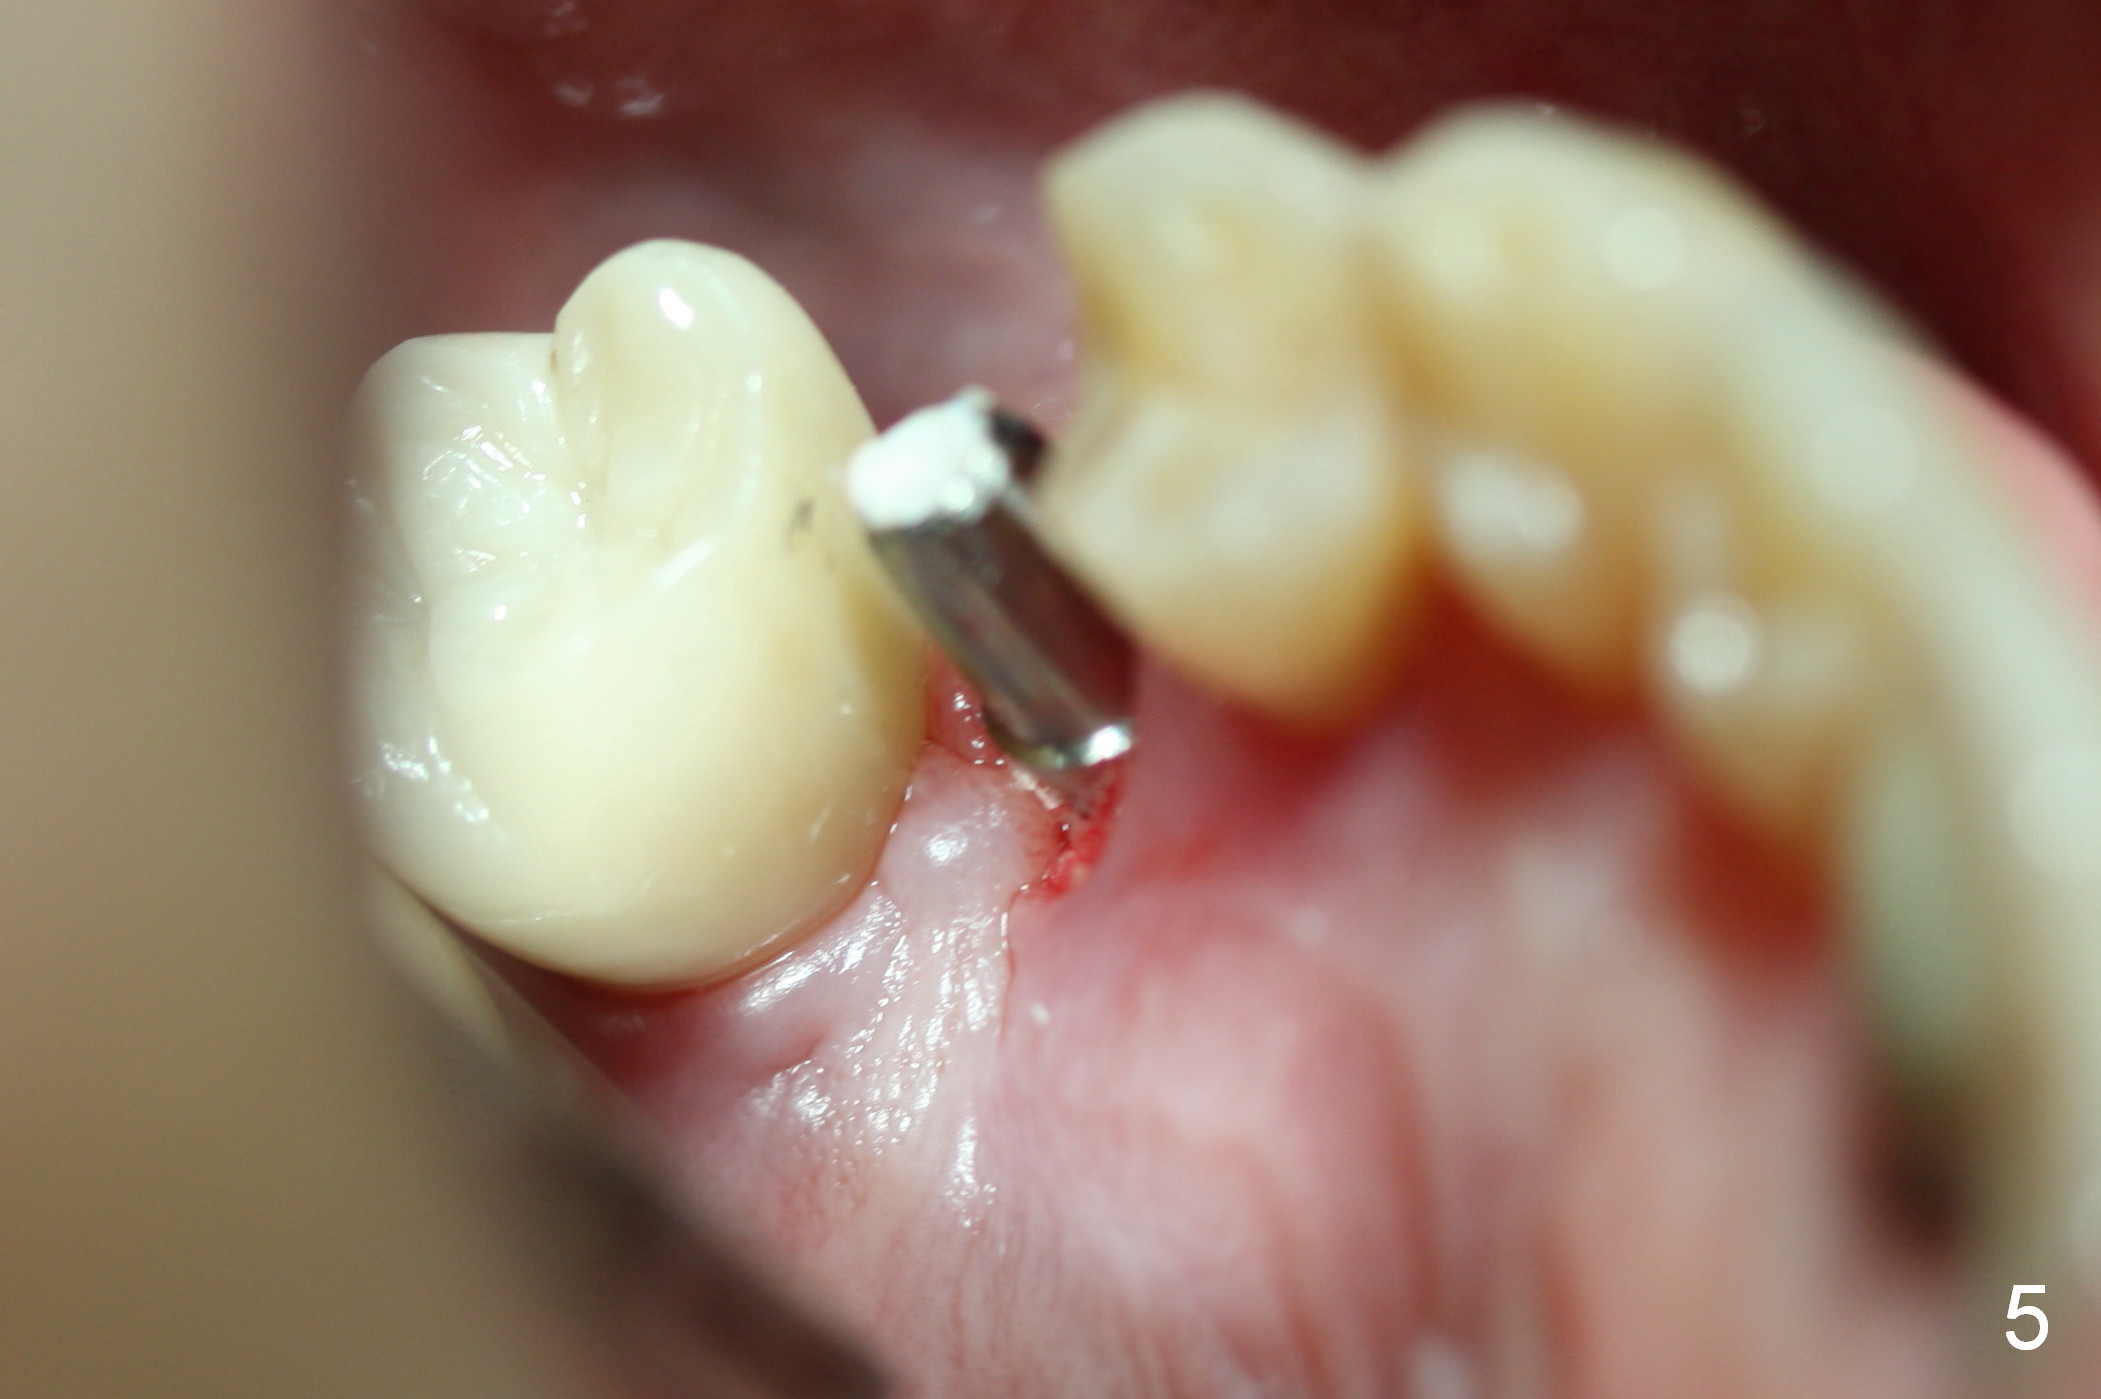

The distal buccal (Fig.1) and palatal (Fig.2) papillae (*) are recessive at the tooth #4. Following extraction and use of 3.8 mm Magic Drill, a 4.5x13 mm implant is placed lower than the mesial crest (Fig.3) to reduce the chance of the distal implant thread exposure. The latter is a measure to decrease peri-implantitis. A 4.5x5.7(4) mm pair abutment is placed (Fig.4,5). The remaining socket is filled with allograft/Osteogen placement. The large space between #3 and 4 implants is occupied by the healthy gingiva, where bone graft cannot get in.